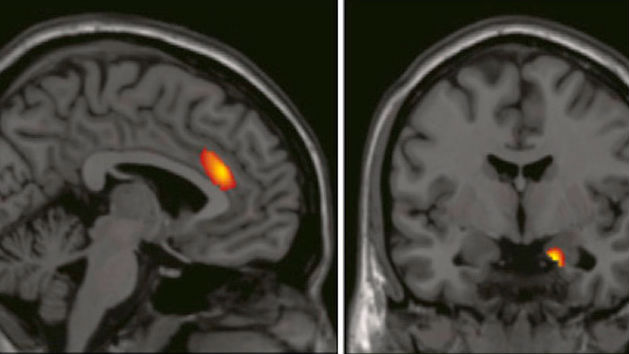

The researchers (though I can’t help but smile as I write that, given the co-authorship of both Firth and Tom Feilden, the science correspondent for BBC Radio 4’s Today program, or programme if you want to stay true to the original) found a correlation between brain structure and political orientation in a group of young adults. Specifically, they conducted structural MRI scans of healthy volunteers, who had identified their political attitude on a 5-point scale, from “very liberal” to “very conservative,” and found that people who were more liberal also had increased gray matter in the anterior cingulated cortex (ACC), while those who were more conservative had increased volume in the right amygdala.

Their working theory is that certain emotional and cognitive traits, which are partly reflected in the differing sizes of the ACC and amygdala, may influence the formation of political attitudes. For instance, the amygdala has been tied to fear processing, and prior studies have found a correlation between larger amygdala size and greater experienced fear. The ACC, on the other hand, has been linked to the management of uncertainty. So, a larger ACC – more tolerance of uncertainty and conflict. Still, it’s a long leap of logic and interpretation to take the next step and say larger amygdala, greater fear, ah yes, conservatives are fearful of change, and larger ACC, greater conflict and uncertainty monitoring, why, of course, liberals are more open to change. And while the authors don’t make those claims outright, they certainly do suggest them.